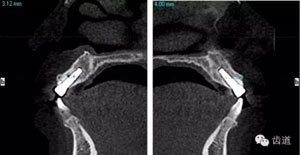

術(shù)后CT

戴牙后CT